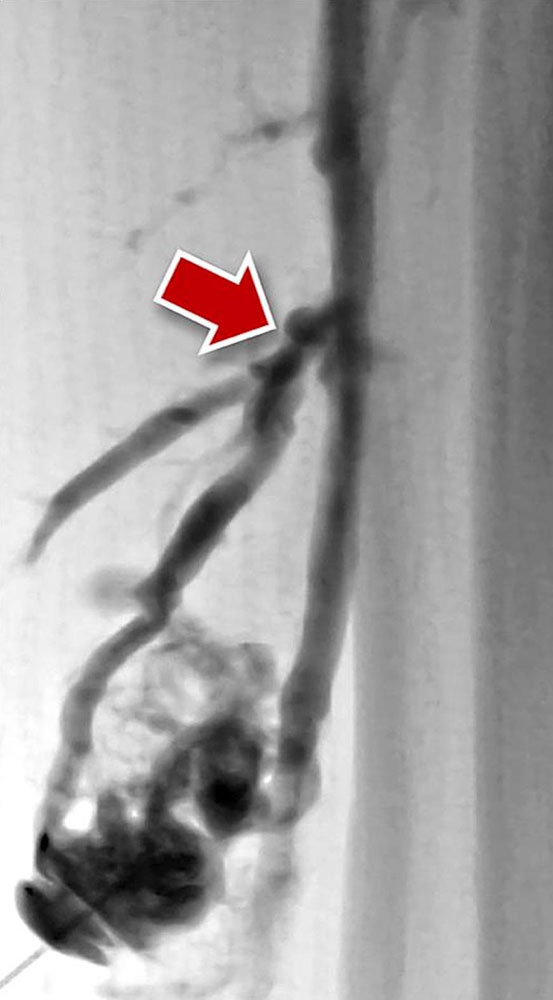

Venous malformations are typically tubular or lobulated, sponge-like dysplastic vascular spaces, which are almost always connected to very small or larger draining veins (communicating veins). Contrast filling defects within the venous malformation correspond to intraluminal thrombi or phleboliths. Direct puncture of the lesion with a needle and subsequent injection of contrast medium aims to identify larger veins of the malformation communicating with the deep venous system immediately prior to sclerotherapy. Any larger communicating veins should be closed. In addition, the contrast injection confirms the needle position and provides an estimate of the size and volume of the punctured part of the venous malformation.